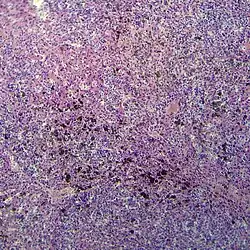

Мелано́ма (лат. melanoma, melanoma malignum ← др.-греч. μέλας «чёрный» + -ομα «опухоль»), уст. меланобласто́ма — злокачественная опухоль, развивающаяся из меланоцитов — пигментных клеток, продуцирующих меланины. Наряду с плоскоклеточным и базальноклеточным раком кожи относится к злокачественным опухолям кожи. Преимущественно локализуется в коже, реже — сетчатке глаза, слизистых оболочках (полость рта, влагалище, прямая кишка). Одна из наиболее опасных злокачественных опухолей человека, часто рецидивирующая и метастазирующая лимфогенным и гематогенным путём почти во все органы. Особенностью является слабая ответная реакция организма или её отсутствие, из-за чего меланома зачастую стремительно прогрессирует. Преимущественно радиогенная опухоль, чаще всего вызываемая облучением кожи ультрафиолетовым излучением.

Варианты

Клинические формы:

- Поверхностно-распространяющаяся меланома, 70 % случаев: как правило развивается у женщин, характеризуется горизонтальным ростом и в общем имеет благоприятный прогноз.

- Узловая меланома (нодулярная), 15 %: чаще у мужчин, характеризуется ростом в толщу кожи, считается самым неблагоприятным в плане прогноза типом.

- Акролентигинозная меланома (лат. Acral Lentigo Maligna) 10 %: известна и как подногтевая меланома. Растёт также на кончиках пальцев, ладонях. Встречается чаще всего у темнокожих лиц.

- Лентигинозная меланома, (лат. Lentigo Maligna, злокачественная веснушка Хатчинсона, меланоз Дюбрейля) 5 %: развивается на фоне пигментного пятна (родинки), как правило на лице, главным образом у женщин. Характеризуется горизонтальным, медленным ростом и имеет наиболее благоприятный прогноз.

- Ахроматическая меланома (беспигментная) очень редко.